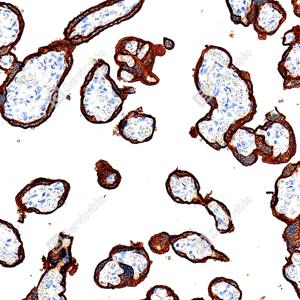

| IHC检测Placental alkaline phosphatase (PLAP)蛋白(货号 GB152546). 样品: 人胎盘, 4%多聚甲醛 (货号G1101) 固定12-24小时. 抗原修复: Tris-EDTA抗原修复液(pH 9.0) (G1203), 100℃, 25分钟. —抗: 1: 1000稀释, 4℃ 孵育过夜. 二抗: S-vision免疫组化多聚二抗(山羊抗兔),即用型 (货号G1302), 室温孵育20分钟. |

| IHC检测Placental alkaline phosphatase (PLAP)蛋白(货号 GB152546). 样品: 人胎盘, 4%多聚甲醛 (货号G1101) 固定12-24小时. 抗原修复: Tris-EDTA抗原修复液(pH 9.0) (G1203), 100℃, 25分钟. —抗: 1: 2000稀释, 4℃ 孵育过夜. 二抗: S-vision免疫组化多聚二抗(山羊抗兔),即用型 (货号G1302), 室温孵育20分钟. |